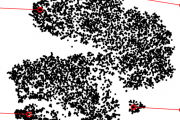

Phenotyping A key question in learning from clinical routine imaging data is whether we can identify coherent patterns that re-occur across a population, and at the same time are linked to clinically relevant patientparameters. Here, we present a feature learning and clustering approach that groups 3D imaging data based on visual features at corresponding anatomical regions extracted from clinical routine imaging data without any supervision. (Hofmanninger et al, 2016)